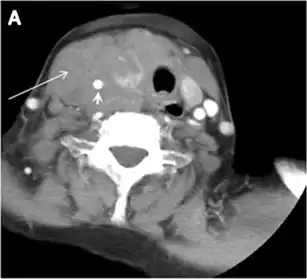

Surgery is the primary mode of treatment for DTCs. Post total thyroidectomy radioactive iodine (RAI) ablation is an option, especially in patients with distant metastasis, tumours larger than 4 cm, or extra-thyroidal disease extension. Ultrasound examination is usually adequate in evaluating primary tumours and cervical lymph nodes. Preoperative cross-sectional imaging with CT or MRI is indicated if there is a concern for local invasion that may alter the patient's staging as well as surgical approach (Figs. 4, 55 and 6)6) . Some thyroid primaries may be small, diffuse, or multifocal and therefore may be occult on imaging (Fig. 4) .[1]

Fig. 4. A 45-year-old male patient presented with anterior mediastinal metastatic PTC lesions and occult primary on imaging. Histopathology examination of the resected thyroid gland revealed micro-foci of PTC; the largest, in the isthmus, measured 4 mm. a transverse greyscale ultrasound of the thyroid demonstrates homogeneous gland with normal echogenicity and size. No focal lesion or micro-calcifications. b Non-enhanced CT scan obtained as part of PET/CT examination shows a heterogeneous, large, relatively dense anterior mediastinal mass (white arrow) with peripheral calcification (arrowheads). Thyroid gland has normal CT appearance with no abnormal FDG uptake (not shown).[1] -